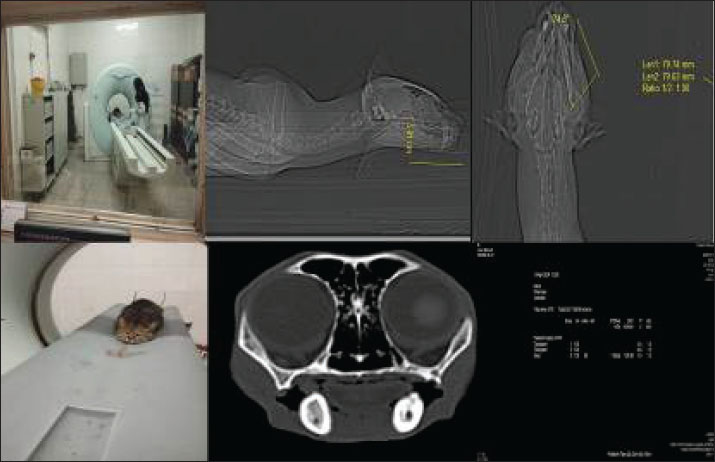

Fig. 1. High-resolution computed tomography imaging of a wild cat subject undergoing diagnostic evaluation for an oronasal fistula, highlighting the integration of advanced imaging modalities in preclinical research. This non-invasive approach enables precise fistula morphology assessment and anatomical mapping, thereby informing the development of bioengineered scaffolds and microbiome-targeted therapies to optimize wound closure and tissue regeneration.

Clinical examination and CT scan revealed an ONF measuring approximately 11 mm (caudal-to-rostral length) × 8 mm (width) at the level of the upper right canine, along with an OCF in the right lower canine tooth (Figs. 1 and 2) (Watanabe et al., 2022). Residual dentition included only the maxillary and mandibular incisors and second premolars, with no clinical evidence of gingivitis or periodontitis. Serological testing for Feline leukemia virus and Feline immunodeficiency virus yielded negative results (Little et al., 2011).

On POD 75, CT (Aquilion Prime SP; Canon Medical Systems) performed at the University of Tehran’s Veterinary Teaching Hospital demonstrated excellent soft tissue integration, with the surgical site appearing indistinguishable from surrounding healthy tissue in both nasal and oral regions. As shown in Fig. 6, the implant was radiographically undetectable with early signs of osseous healing. At 6- and 10-month follow-ups, the wildcats maintained clinical improvement, normal feeding behavior, and stable body weight.